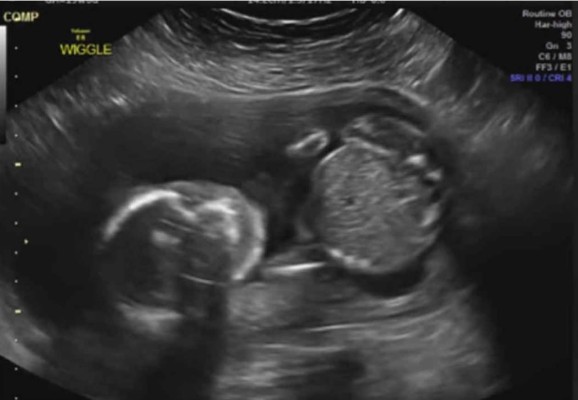

Ultrasonido muestra a un bebé dándose un puño en la cara

El video de un ultrasonido que muestra a un bebé dándose un puño en la cara, se ha vuelto viral y sorprende a todos aquellos que lo ven. Mira el video.

Dave Watson (37) y Vannesa (32), una pareja de Witchi en Kansas, Estados Unidos, estaban preparados para ver a su hijo Edward en sus 20 semanas de gestación y se llevaron la gran sorpresa de su vida, al ver que repentinamente su bebé se dio un puño en la cara.

'Estábamos viendo el ultrasonido y de repente sucedió, la enfermera se río y dijo que lo que había visto era nuevo para ella”, dijo Dave a los medios locales. 'Vanessa pensó que nuestro hijo se había hecho daño a si mismo', añadió.

Según los informes médicos, el bebé está muy bien y no presenta ninguna conmoción cerebral. Mira el impresionante video.